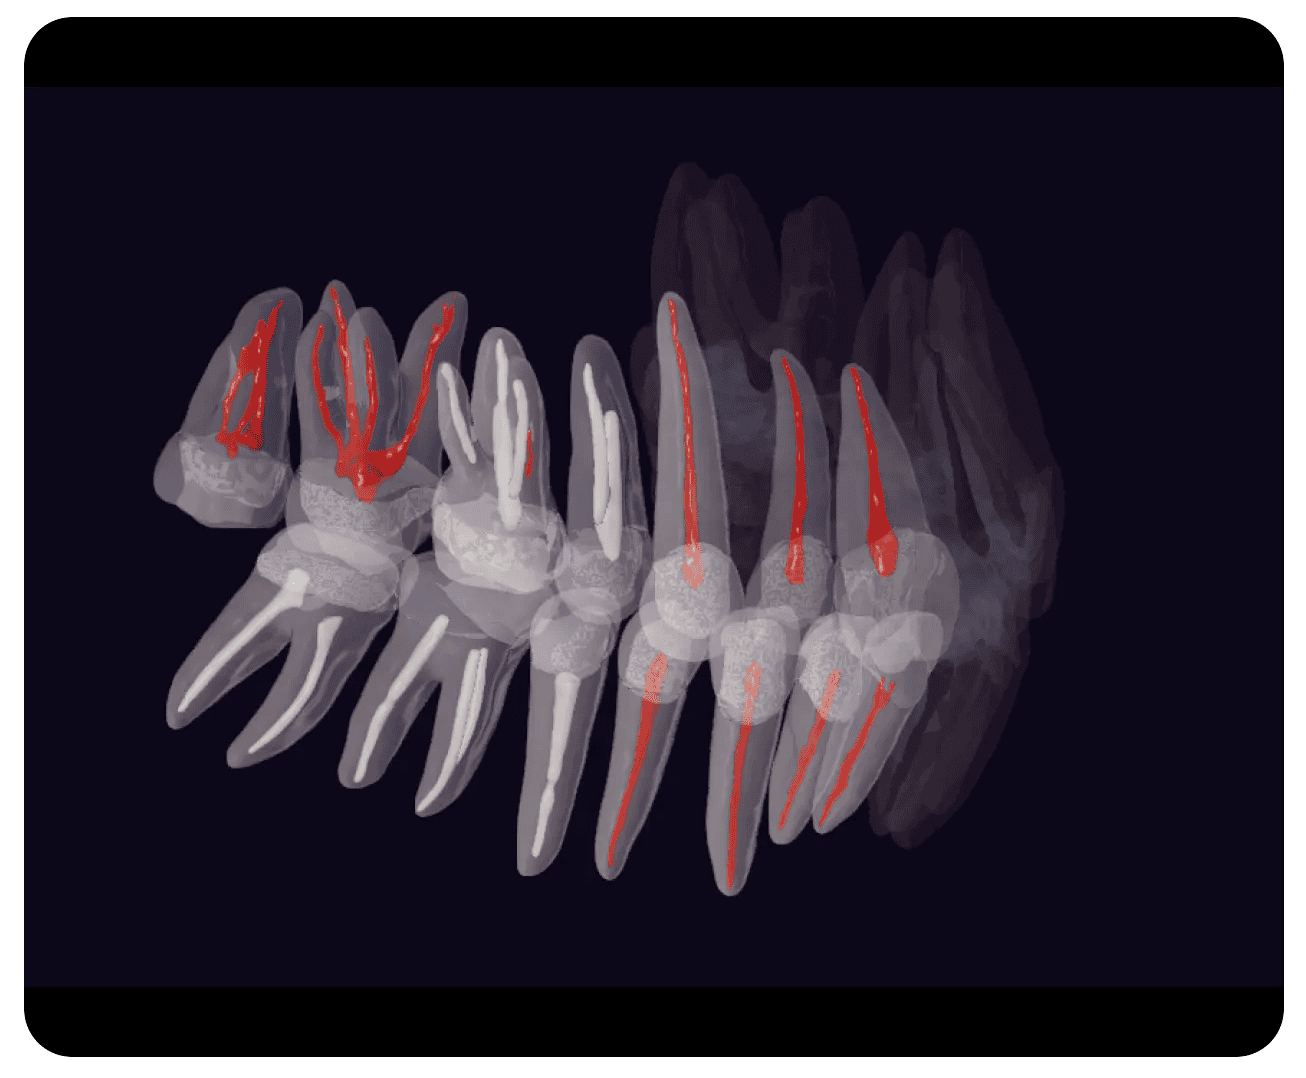

Funcția de segmentare a patologiilor include filtre pentru activarea și dezactivarea condițiilor: Parodontale, Restaurări, Endodontice. Fiecare buton activează o categorie specifică de patologii, care sunt vizualizate grafic în volumul 3D.

Segmentarea canalelor radiculare

Segmentare patologii